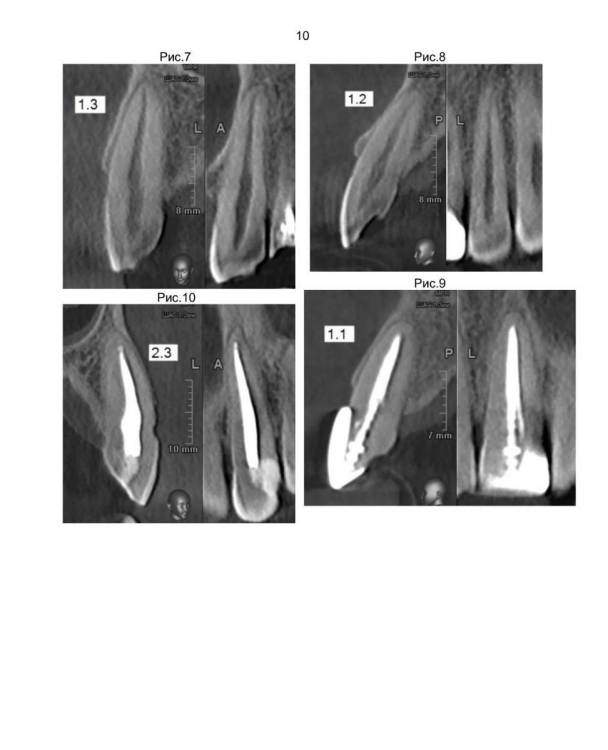

Врач стоматолог написал планы лечения. Больше всего меня смущает удаление трех верхних зубов 1.4, 1.5, 1.6 т.к. на концах корней у этих зубов развиваются опухоли, и установка на их место имплантов сразу после удаления. Правильно ли это? Просто до этого слышал, что перед установкой импланта требуется около трех месяц на заживление. Стоматолог говорит, что надо сразу установить импланты, что бы избежать деформацию десны. Потом через примерно три месяца на эти три импланта будут ставиться коронки.